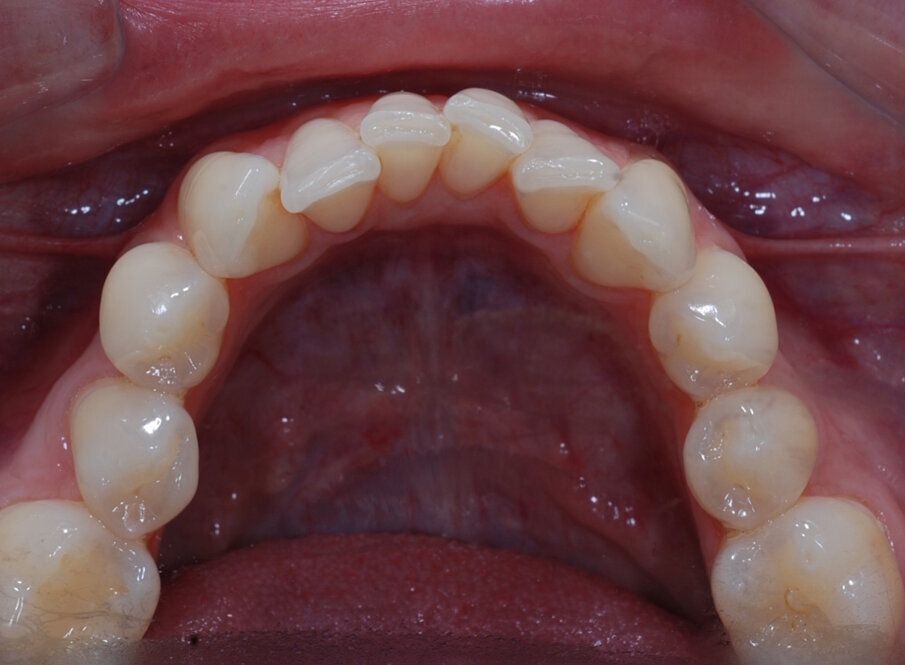

Fig. 20: Post treatment occlusal

The patient was very satisfied with the results, especially the fact I was able to improve her smile without affecting the integrity of the enamel. I sent before and after images to the patient at the end of her treatment pathway so that she could see the difference, and she was amazed at how much the aesthetics of her teeth had changed. I was also very happy with the outcome – with the help of the IAS Academy and digital planning tools, treatment was safe and predictable.